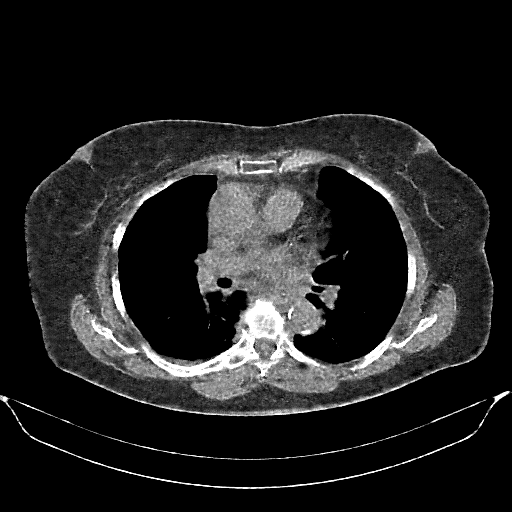

Generated VENOUS CT scan (A→B translation)

Full window (WL 1023.5, WW 4095 β†’ Low βˆ’1024, High +3071)

Actual HU range: [-1024.0, 1390.1]

Lung window (WL -600, WW 1500 β†’ Low βˆ’1350, High +150)

Actual HU range: [-1259.5, 150.0]

Mediastinum window (WL 40, WW 400 β†’ Low βˆ’160, High +240)

Actual HU range: [-160.0, 240.0]